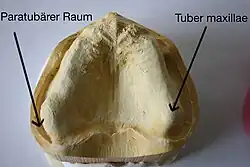

Die Beißkraft wird hauptsächlich von den vier Muskeln Musculus masseter (Kaumuskel), Musculus temporalis (Schläfenmuskel), Musculus pterygoideus medialis (innerer Flügelmuskel) und Musculus pterygoideus lateralis (äußerer Flügelmuskel) ausgeübt. Die drei erstgenannten Muskeln sind die Elevatoren, demnach diejenigen Muskel, die den Unterkiefer heben und den Zusammenbiss bewirken. Der Letztgenannte ist ein Führungsmuskel (für die Vorschubbewegung des Unterkiefers). Die maximale Beißkraft zwischen den Molaren eines Totalprothesenträgers (118 N ≈ 12 kp) ist im Vergleich zum vollbezahnten Patienten (1470 N ≈ 150 kp) erheblich reduziert. Damit sinkt auch die Kaueffizienz bei Prothesenträgern. Das Zerkleinern der Nahrung dauert vier- bis fünfmal so lange wie bei Vollbezahnten.[34] Das Abbeißen ist mit einer Totalprothese nur eingeschränkt möglich. Voraussetzung ist, dass die Tubera maxillae ausgeprägt sind und die Prothese in den paratubären Raum reicht und die Tubera umfasst, sonst wird die Oberkieferprothese abgehebelt. Ist der Tuber maxillae nur einseitig ausgebildet, so kann gegebenenfalls mit der kontralateralen Seite abgebissen werden. Sonst muss die Nahrung zerkleinert statt abgebissen werden.